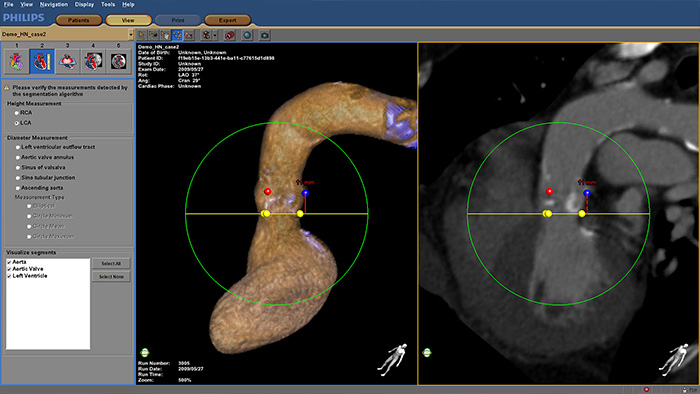

HeartNavigator

Increase confidence and ease during transcatheter aortic valve replacement (TAVR) and other challenging SHD procedures. The immersive user experience is highly automated to simplify planning, device selection and projection angle selection. During procedures, it provides live image guidance to support device positioning.